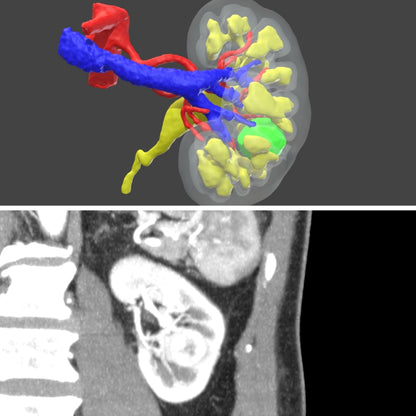

Surgical planning - Digital 3D model for urology

Surgical planning - digital model

Only for urology

Plan your next surgery with a 3D model of the patient's exact anatomy. This planning is done based on the CT scans.